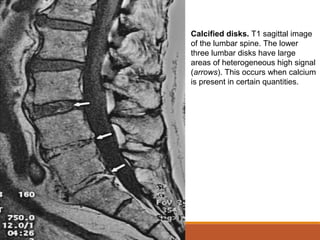

Calcified disks. T1 sagittal image

of the lumbar spine. The lower

three lumbar disks have large

areas of heterogeneous high signal

(arrows). This occurs when calcium

is present in certain quantities.